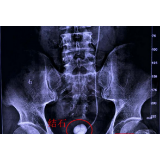

陶先生术前检查影像。

陶先生三年前做过一次结石手术,术后医生在其体内放了一根双J管。原本按医嘱一个月后,要去医院取出。因为已经习惯了双J管,没有太多不适,加之一些事情耽误了,取双J管这事便一直没有再管。没想到近期因为结石病就引发了一系列腰腹疼痛、排尿不畅等症状。在长沙南湖医院结石中心检查发现,其双J管连着膀胱的一端以及肾脏端,都布满了结石。好在经过南湖医院结石中心的专家组认真操作,结石和双J管均已成功取出!